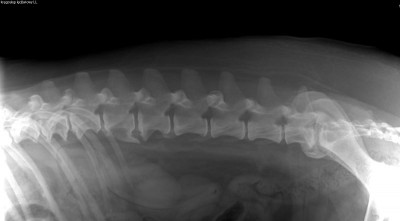

Na pierwszy rzut oka widać, że psiak ma znaczne problemy z poruszaniem się. Bamberek porusza się sztywno i stwierdzono u niego kulawiznę II stopnia na prawej tylnej łapce. Ma również widocznie osłabiony odruch korektury, zwiększone napięcie mięśni lędźwiowo-biodrowych, ograniczenie w odwodzeniu stawów biodrowych oraz obniżenie napięcia mięśniowego mięśni udowych. Na zdjęciach RTG widać u niego dysplazję stawów biodrowych, zmiany zwyrodnieniowe i stany zapalne, które z pewnością sprawiają mu ból :(

Niestety to nie koniec jego ortopedycznych problemów. W badaniu fizykalnym Pan doktor stwierdził zwiększoną bolesność odcinka lędźwiowo-szyjnego kręgosłupa. Na RTG kręgosłupa ma widoczne zmiany typowe dla zaawansowanej postaci zespołu końskiego ogona, zaawansowaną spondylazę a na domiar złego przewężenia w przestrzeniach międzykręgowych m.in. w odcinku szyjnym co ma wpływ na jego czucie (kwestie neurologiczne) i stanowi ryzyko paraliżu w przyszłości :(

Kręgosłup szyjny 1.jpg

Plik ściągnięto 10 raz(y) 24.56 KB

Kręgosłup lędźwiowy 1.jpg

Plik ściągnięto 7 raz(y) 24.88 KB